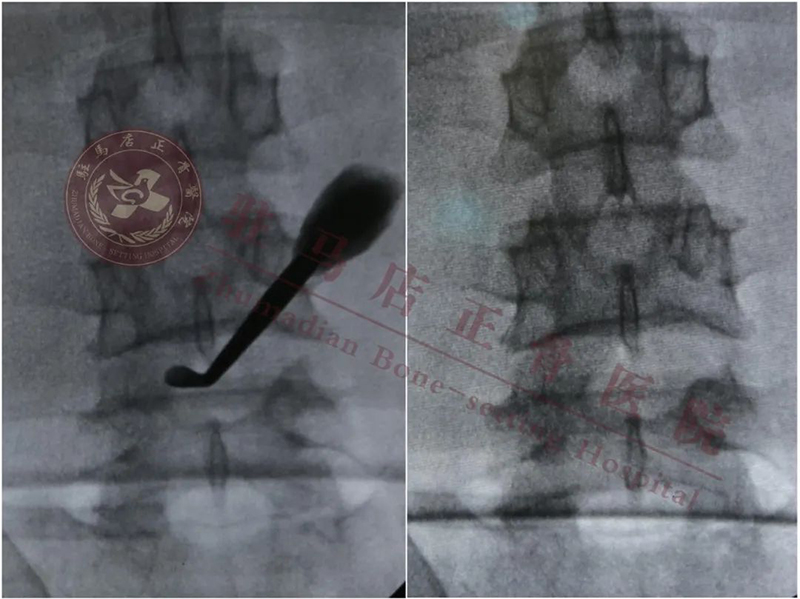

术中定位

植入cage